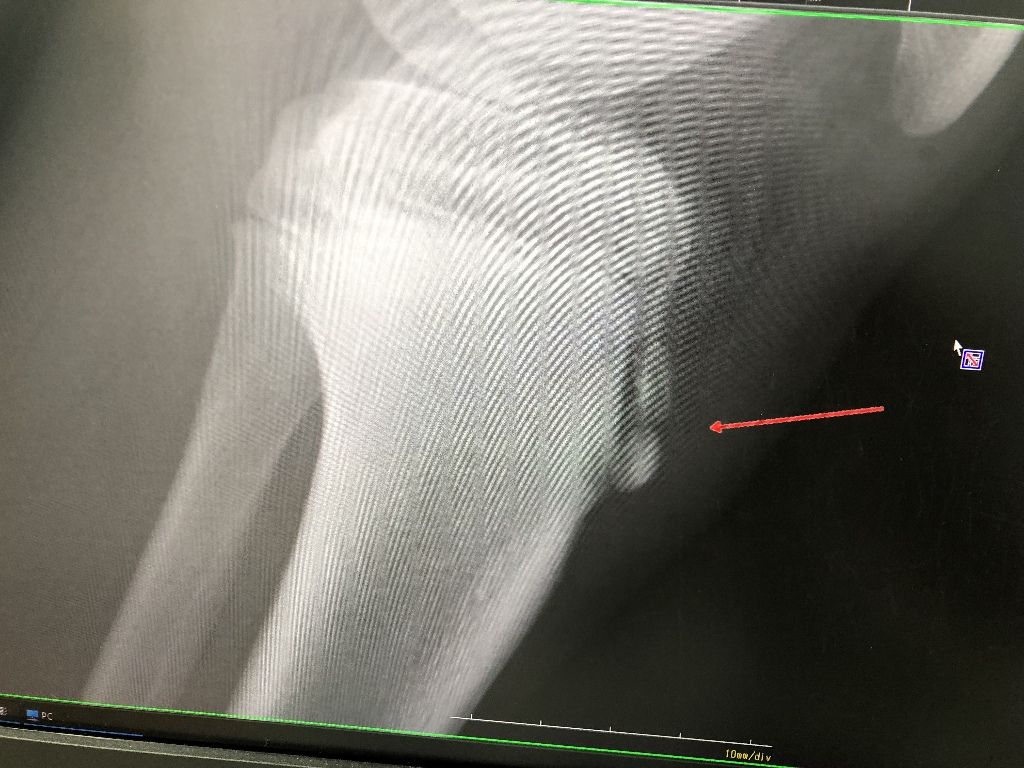

成長痛

この時期に多いのが、成長痛!

寒くて筋肉が硬くなって

そして、走り込みが多いのが原因でしょう

ストレッチをたくさんしましょう!